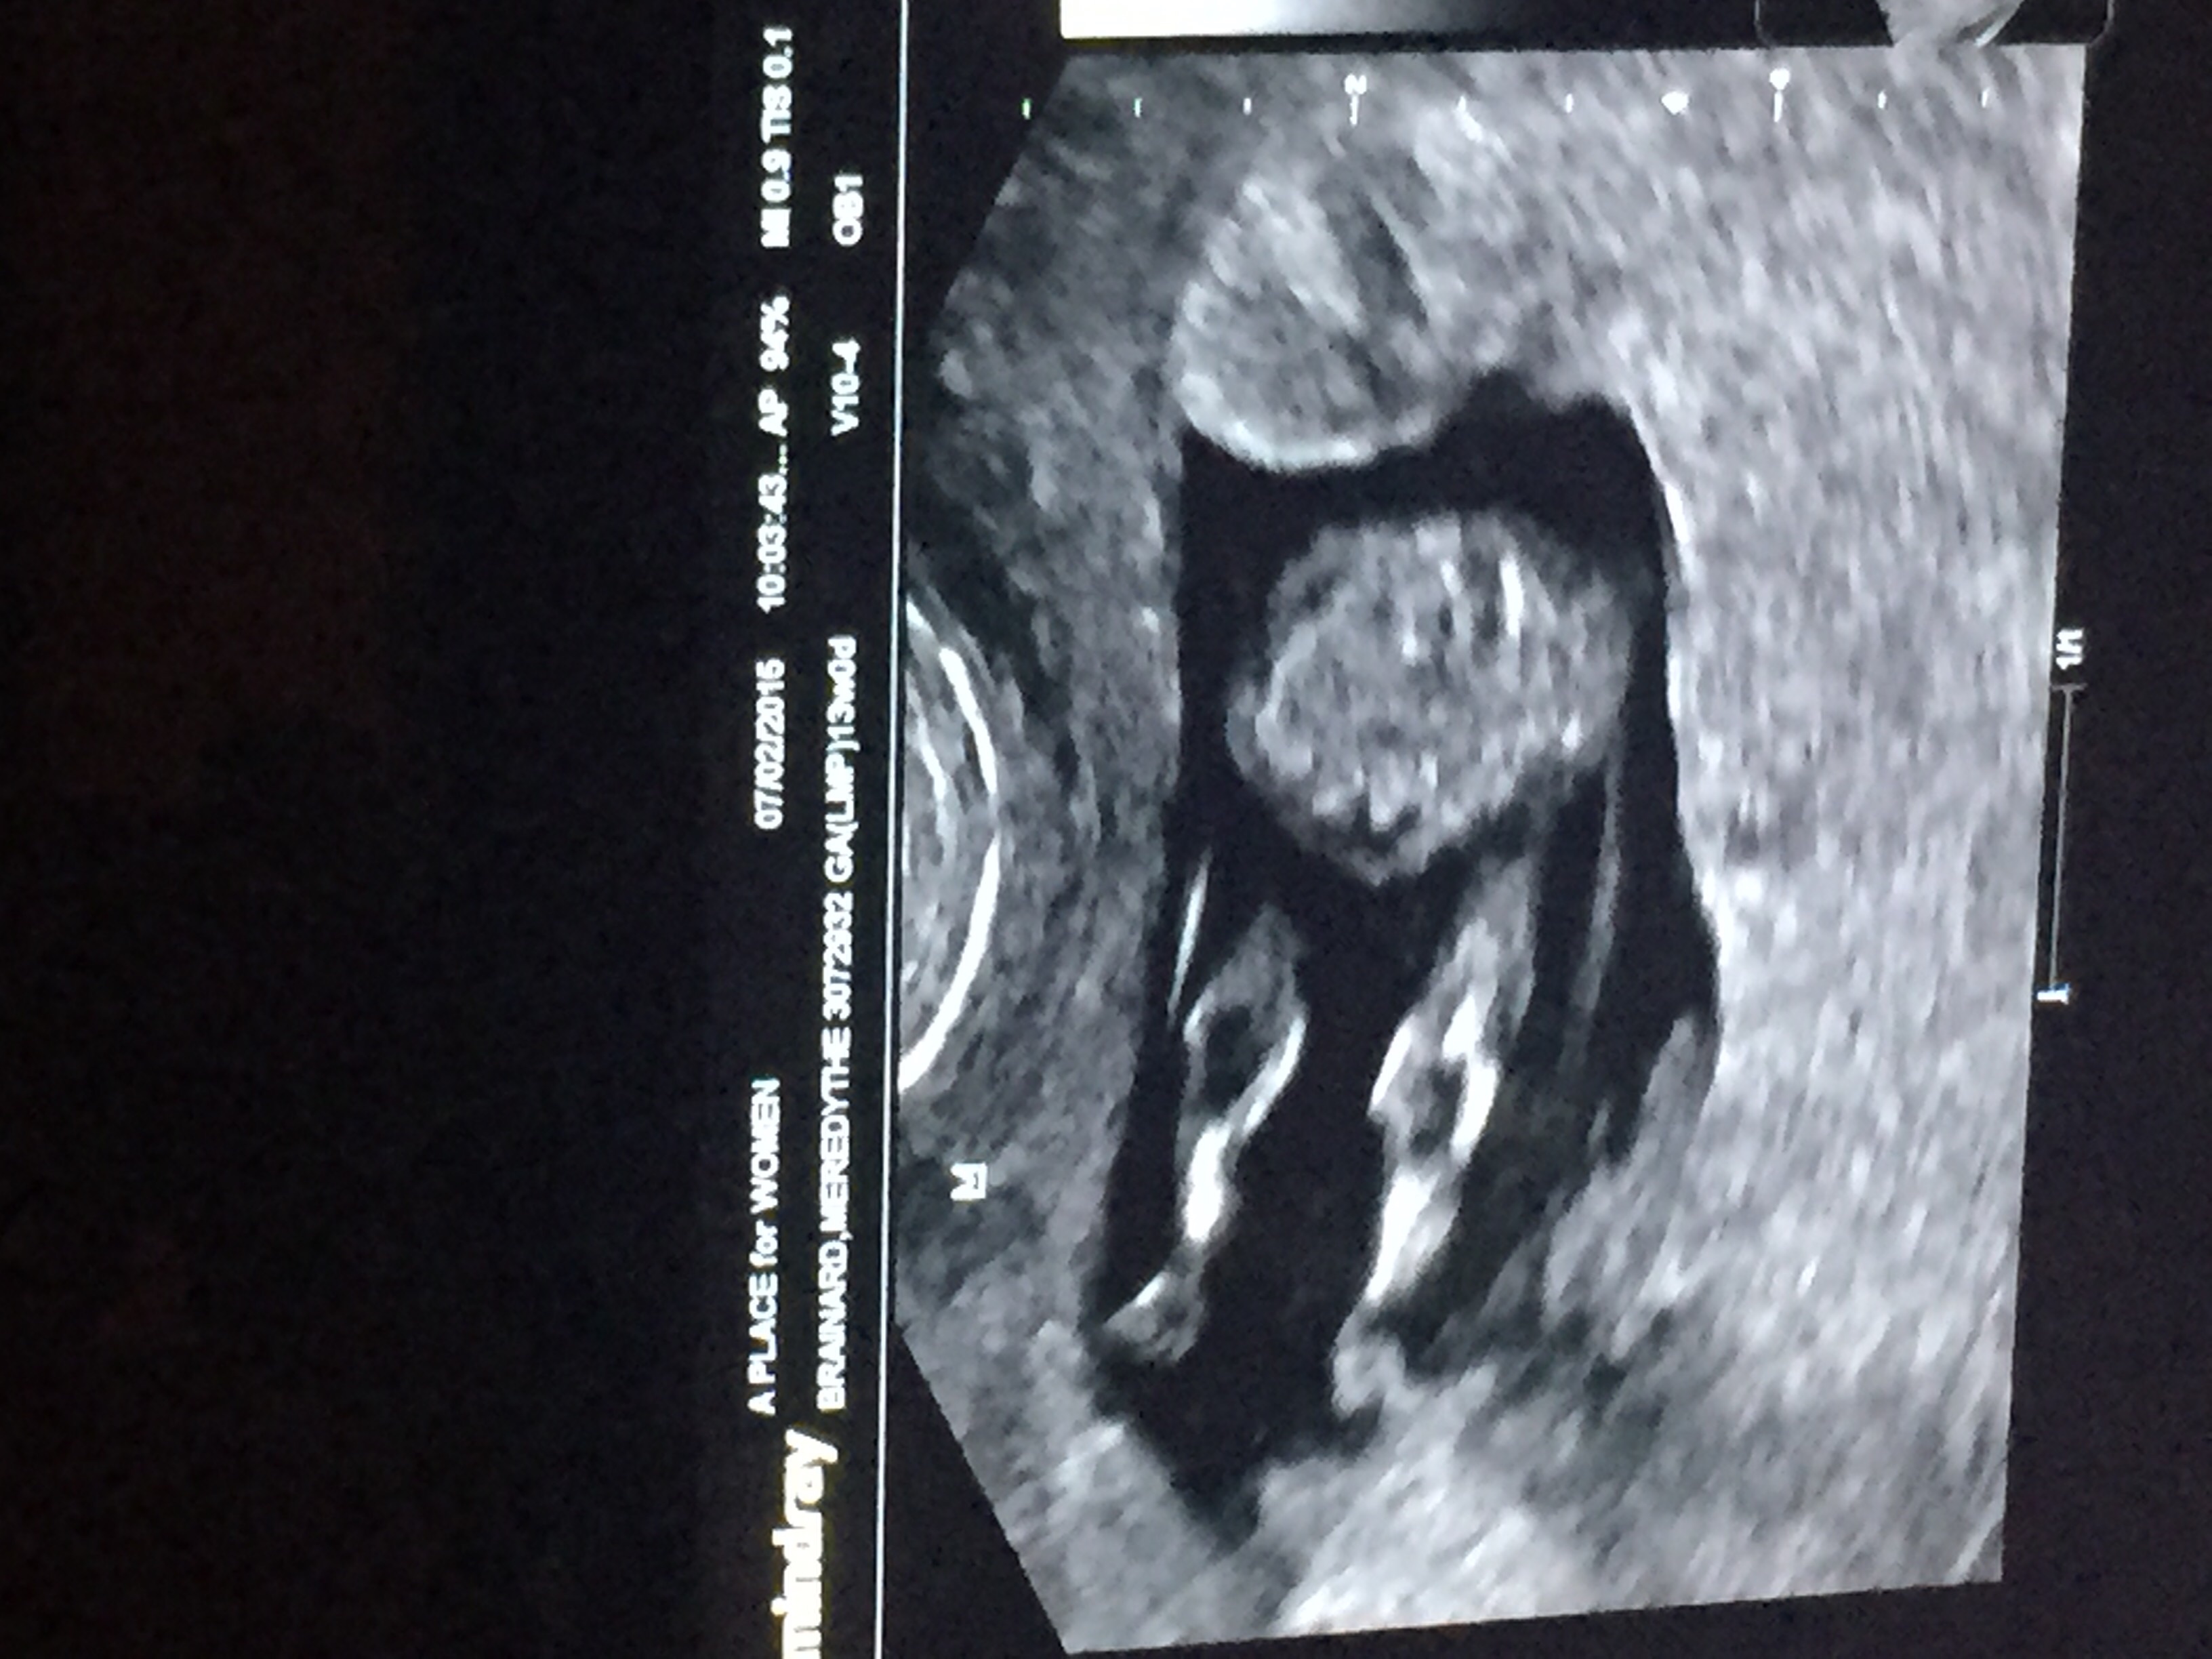

13 weeks 4 days, NT scan all looks fabulous. Heartbeat of 165. Baby was hiccuping and chillaxing! The baby is laying across my abdomen with its feet propped up in my uterus, nice and comfy in there! Placenta is also high, which is good because I was nervous about previa w/ earlier bleeding.